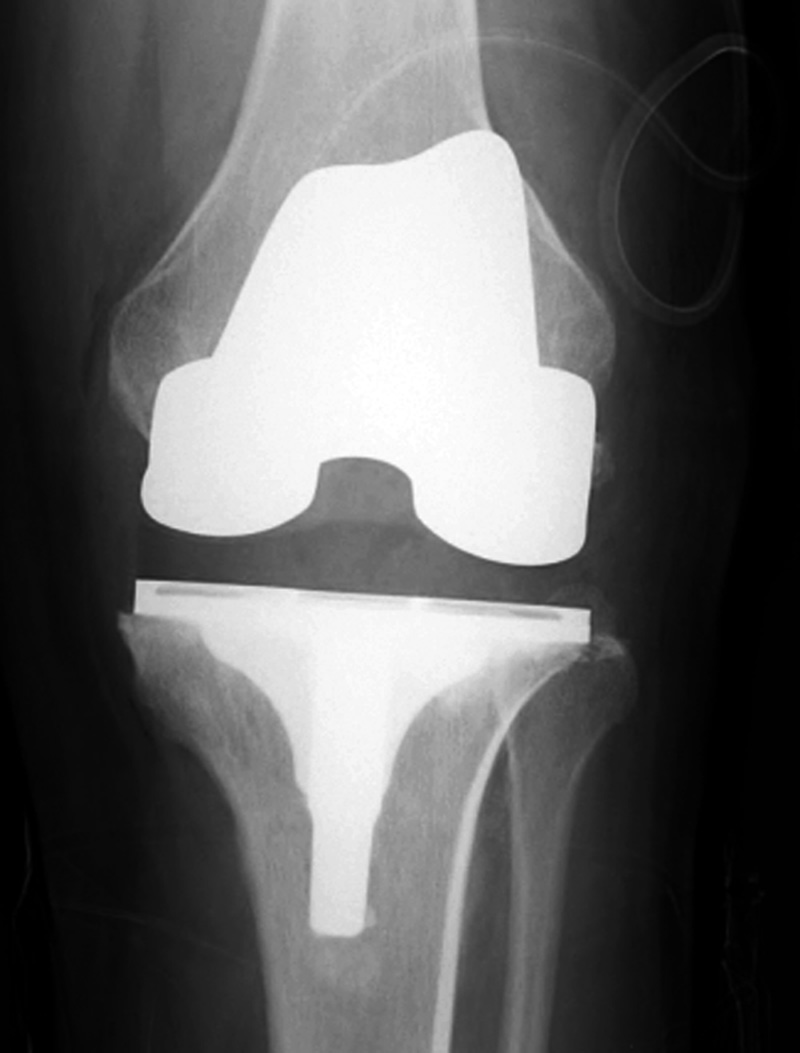

Cruciate retaining total knee arthroplasty (TKA)   Biomet Vanguard 360 Revision Knee System

Cruciate retaining TKA Cruciate retaining TKA Biomet Vanguard 360 knee revision Biomet Vanguard 360 knee revision

68 year-old woman treated for severe left knee osteoarthritis This replaced a loose prior total knee arthroplasty. The patellar button was left in place. A surgical drain is in place, and there is subcutaneous gas from the recent surgery.